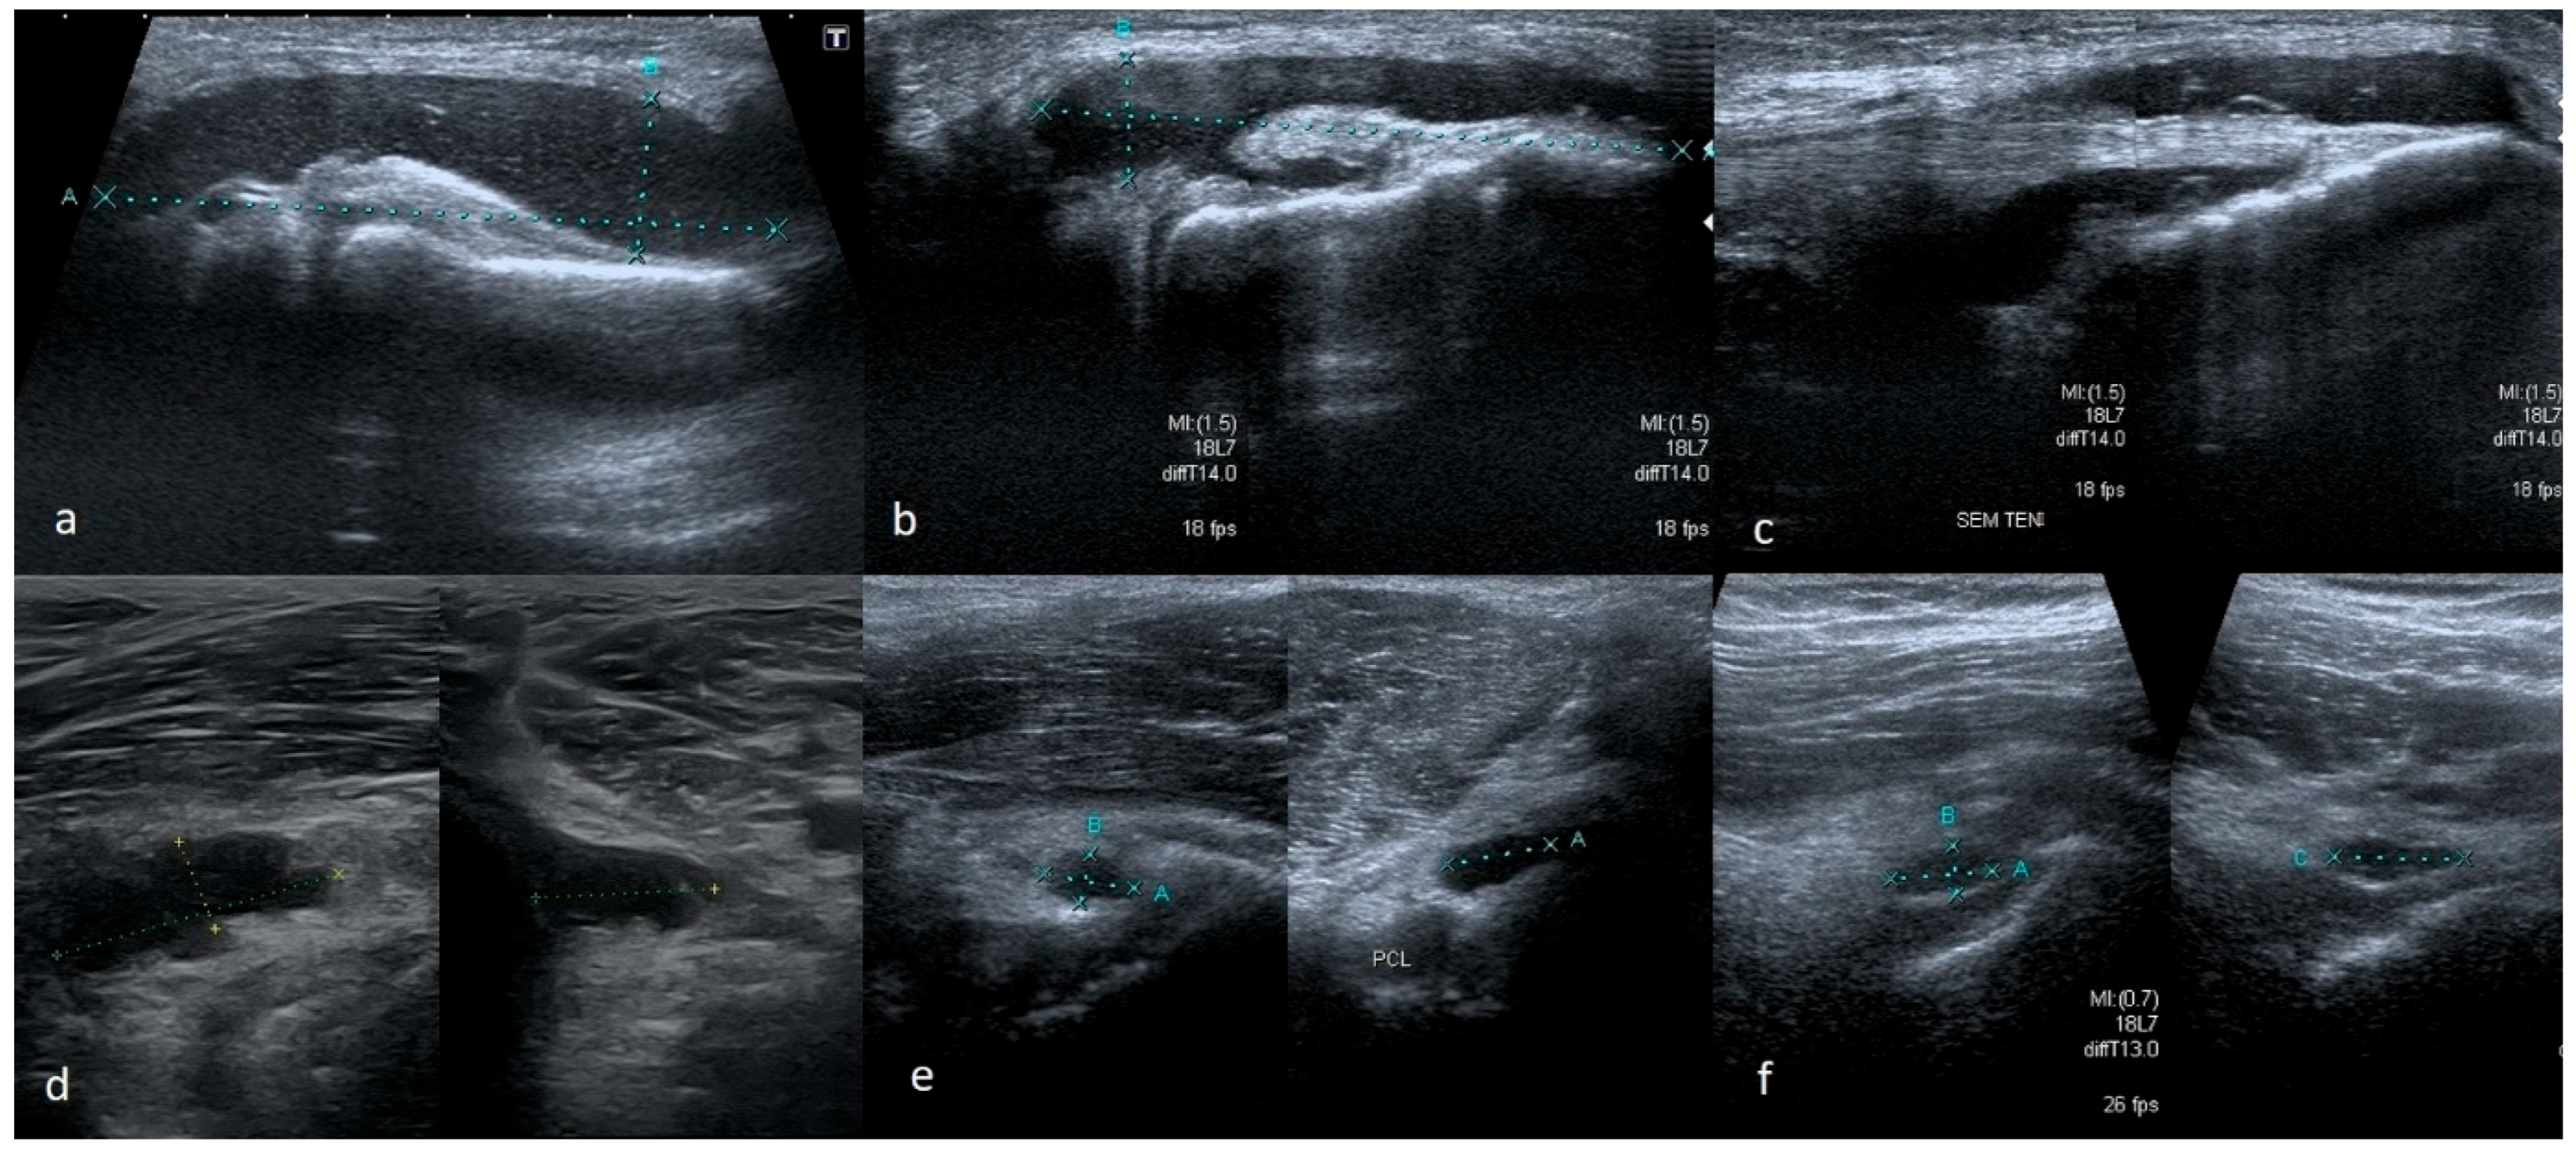

3.1.2. Meniscus Cysts

3.1.3. Bucket-Handle Tears

3.1.4. Meniscal Flap Tears

3.1.5. Degenerative Changes of Menisci